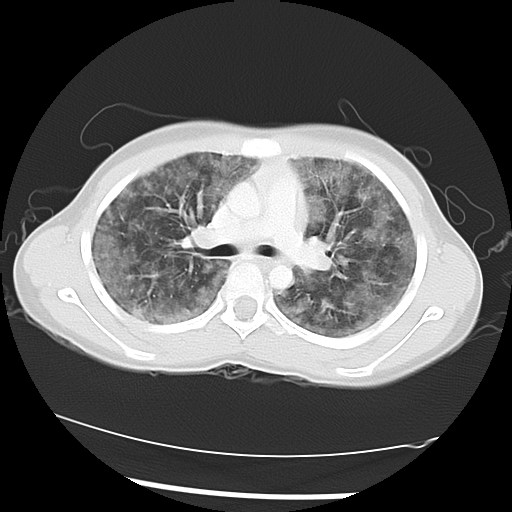

The following screen shows the images from the Chest CT:

| Figure 2-a | Figure 2-b | Figure 2-c |

| Figure 2-d | Figure 2-f |